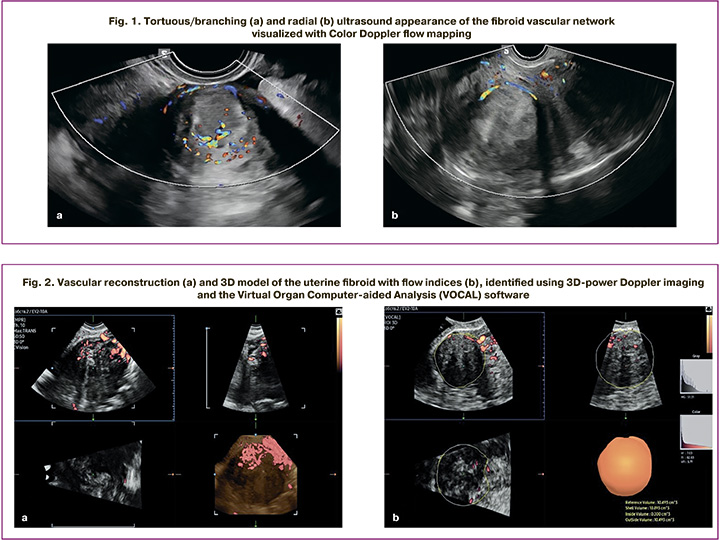

Central and peripheral intratumoral vessels were visualized in two-dimensional Color Doppler flow mapping, followed by a qualitative analysis of their ultrasound morphology. Depending on the number and nature of the vessels, two types of vascular architecture were detected: tortuous/branching architecture – multiple vessels inside the myoma with a tortuous course and/or the presence of clearly visualized branches (Fig. 1a); radial architecture – a single peripherally located vessel without signs of intratumor branching (Fig. 1b).

All patients also underwent a 3D ultrasound examination using power Doppler and specialized VOCAL technology. A 3D-image of each uterine fibroid was obtained using a minimum acquisition angle of 90° and maximum inclusion of the node in the scan volume. The data was then analyzed in VOCAL mode using sequential rotation in 15° increments (12 planes, total angle of 180°). The fibroid contours were sequentially manually traced in the selected plane on each slice, automatically generated by the software during 15° volume rotation around a fixed axis. After contouring on all slices, the software calculated the volume of the fibroid (cm³) and the average echogenicity of the tumor tissue (MG). Additionally, a three-dimensional reconstruction of the fibroid’s vascular network was performed using power Doppler imaging (Fig. 2a). The histogram function was then activated, allowing the program to calculate vascular indices in a semi-automatical mode: vascularization index (%), flow index (relative units), and perfusion index (relative units) (Fig. 2b).